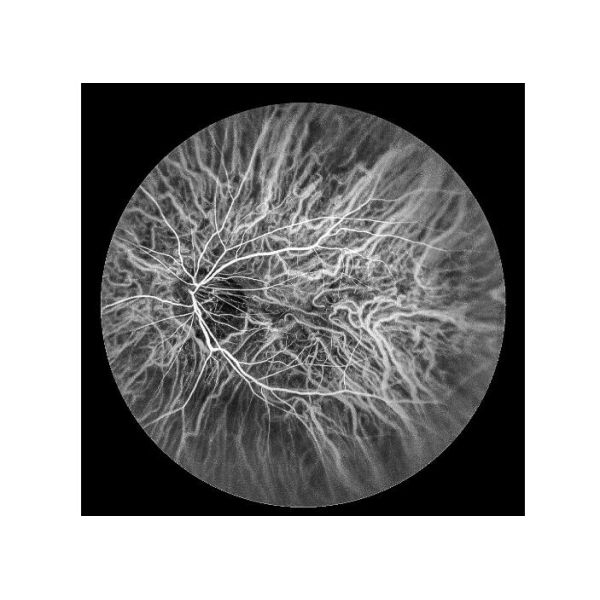

| 2 |  | Indocyanine Green Angiography(ICGA) Choroid vessels and RPE lesions | 1) Golden standard for PVC diagnosis 2) To reveal the details of the choroid cycle 3) Supplement to FFA,to find latent CNV undetected on FFA 4) Mainly to reflect blood vessels condition in early and middle stage, in late stage to reflect the form and function of RPE cells |

Cases

Retina Angiograph Digital 160° Ophthalmic Equipment Images |